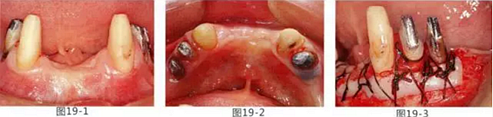

有少數(shù)牙體殘存的病例,需要進行修復處理,將基牙和鉤牙部位的牙周袋去除以及對頰舌側進行FGG(游離齦移植)來獲取附著齦的病例

圖19-1 右下3,4,左下3,4,5殘存牙頰側面照。唇頰側沒有附著齦。

圖19-2 同部位的舌側面照。雖然有1mm左右角化牙齦,但是進行預測切開的話,會使角化牙齦完全消失。

圖19-3 左下3,4,5部位進行FGG(游離齦移植)去除牙周袋以及獲得附著齦。同時進行骨外科處理。相反側也進行同樣的處理。